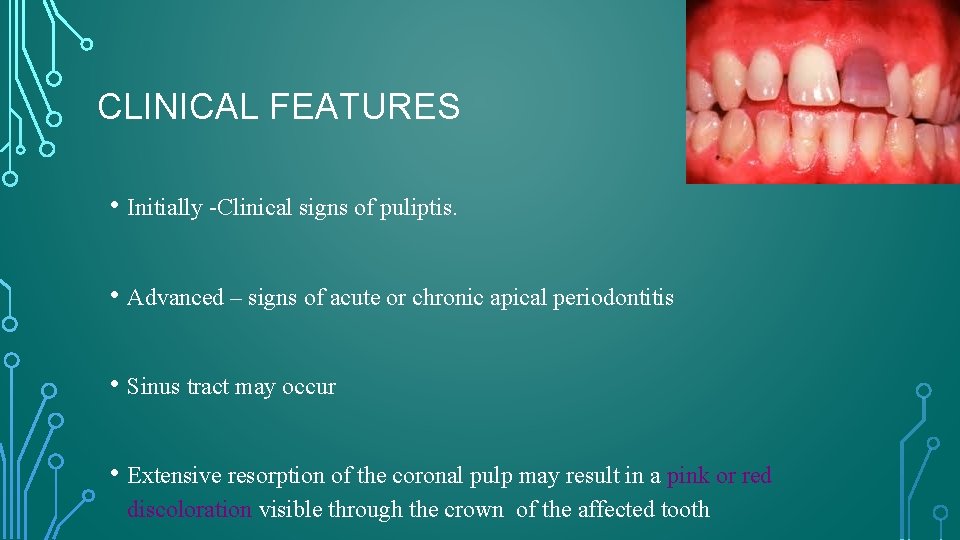

CLINICAL FEATURES • Initially -Clinical signs of puliptis. • Advanced – signs of acute or chronic apical periodontitis • Sinus tract may occur • Extensive resorption of the coronal pulp may result in a pink or red discoloration visible through the crown of the affected tooth